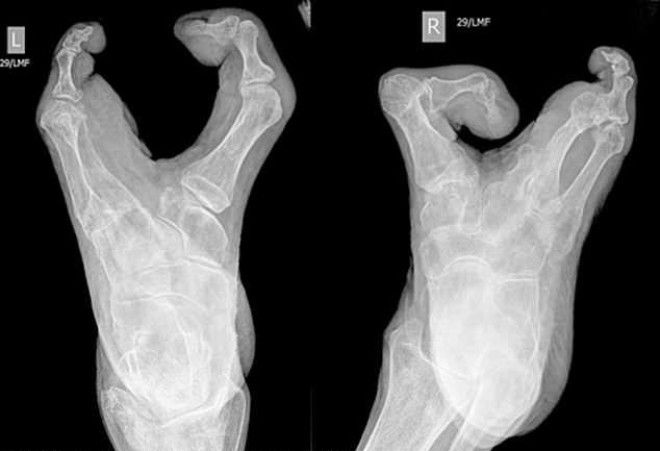

94-летняя жительница графства Восточный Суссекс, Британия, наповал сразила врачей. Она поступила в больницу с подозрением на инфекцию мочевых путей и шокировала медиков своими ногами-клешнями и такими же руками (эктродактилия). Бабушка рассказала, что несмотря на врожденный порок, она всю жизнь справлялась без посторонней помощи, воспитала сына и вяжет для своей семьи.